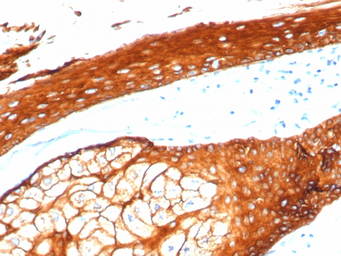

IHC-P analysis of human skin tissue section using GTX02665 Cytokeratin 2 antibody [KRTH/4392R].

IHC-P analysis of human skin tissue section using GTX02665 Cytokeratin 2 antibody [KRTH/4392R].